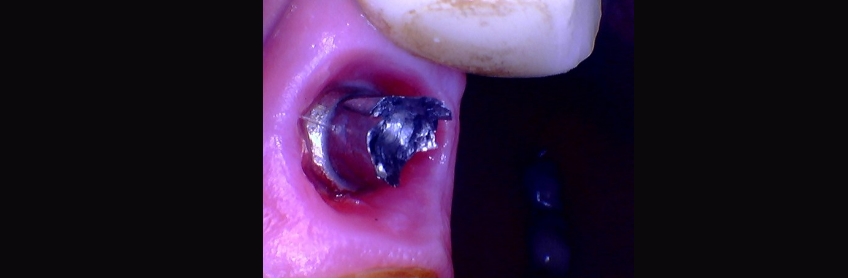

Tip #3: Reach Proper Drilling Length

The next step is to reach the proper drilling depth. And by the way, this will take longer than you think, and you will likely use every drill in the kit. The next step is to use the extraction bolt and ratchet counterclockwise to remove the solid abutment. The result should be the extraction bolt with a solid abutment on it.